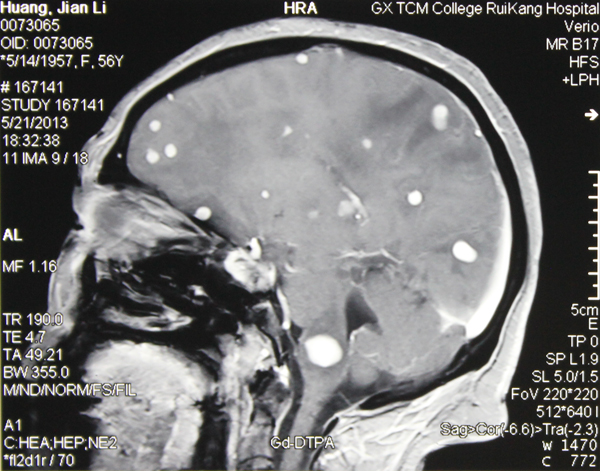

当医生告诉56岁的黄阿姨导致她瘫痪三个月的病因是脑子里面长了真菌,黄阿姨很是疑惑,真菌感染不是灰指甲、脚癣之类的皮肤病吗? 4月份她...